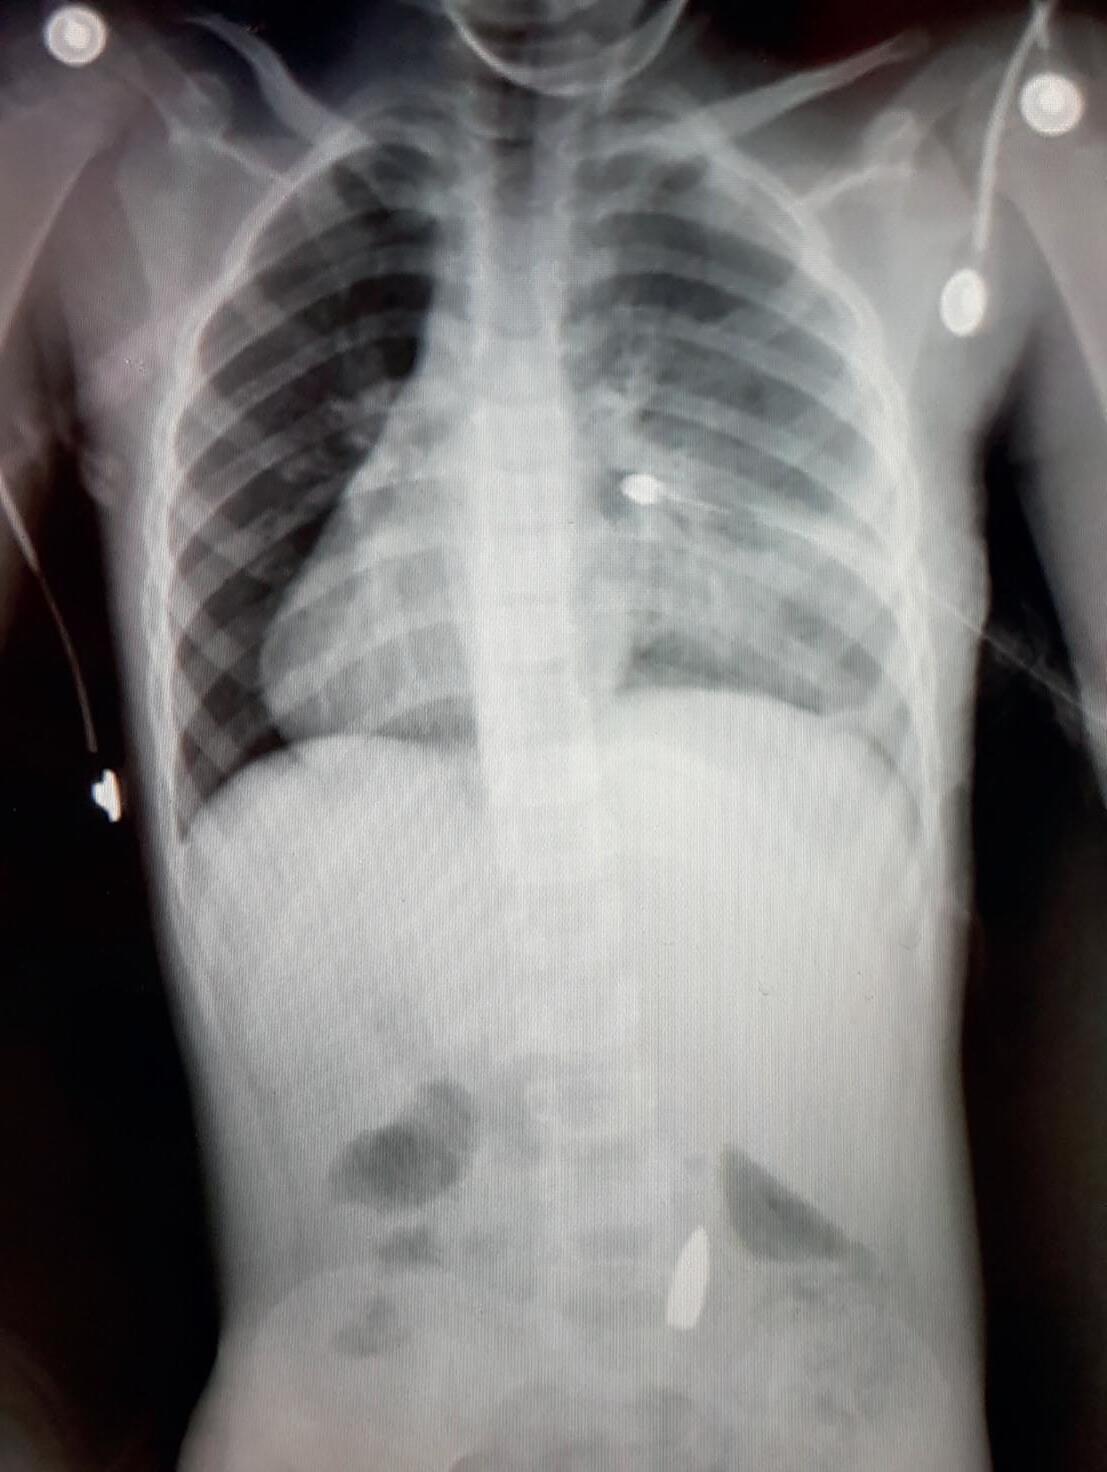

troll på blødningen. Vi eksartikulerte i kneleddet og lot det ligge åpent, for senere å gjøre en femuramputasjon. Hele operasjonen tok 20 minutter til stumpen var bandasjert. Da kom det to blodposer som Mohammad hengte opp. Jeg ble imponert over effektiviteten ved de palestinske sykehusene i akuttsituasjoner. Selv om hele systemet knaket i sammenføyningene, visste alle hva de skulle gjøre når det sto om livet. Så har den palestinske helsetjenesten etter hvert fått stor erfaring med å behandle krigsskader (Bilde 2).

Det var påfallende få pasienter med abdominal- og thoraxskader som kom til sykehuset i forhold til antallet pasienter med ekstremitetsskader. Det var også få barn. Det kan tyde på at evakueringstiden i mange tilfeller var lang. Ambulansene måtte kjøre gjennom en krigssone for å komme til pasientene og ofte måtte de vente på å få tilgang til et område som var bombet. European Gaza sykehus er det tredje største sykehuset på Gazastripen og er tradisjonelt et avansert sykehus som utfører både hjertekirurgi og hjerteintervensjoner, selv om det bare har rundt 300 senger. Det var kontinuerlig bombing, droneangrep og skarpskytterangrep på veiene rundt sykehuset og spesielt i den nærmeste byen, Khan Younis. Derfor var det vanskelig for det faste personalet ved sykehuset å komme seg på jobb da det var livsfarlig å ferdes på veiene. Hver morgen måtte vi ha en opptelling for å se hvilke ressurser som var tilgjengelige. Mange palestinske leger og sykepleiere hadde flyktet fra nord etter hvert som sykehusene ble inntatt og stengt eller ødelagt av den israelske hæren. Flere av dem jobbet som frivillige ved sykehuset sammen med oss utlendinger. Det gjorde at vi kunne drive operasjonsstua på et vis.